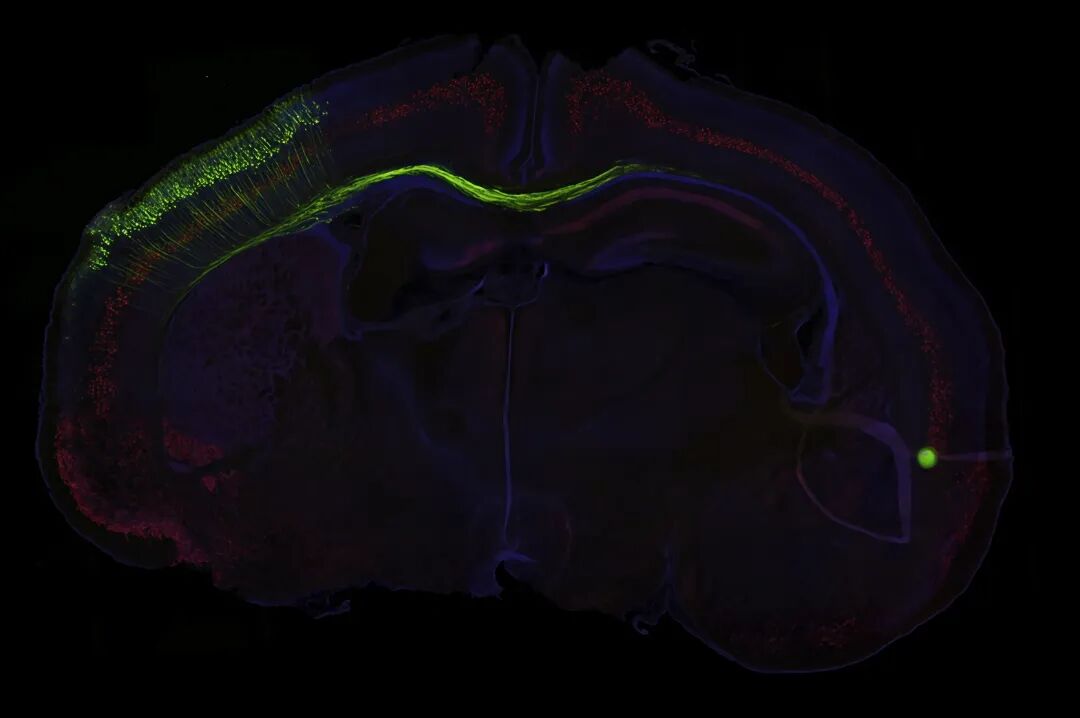

小鼠脑立体定位注射